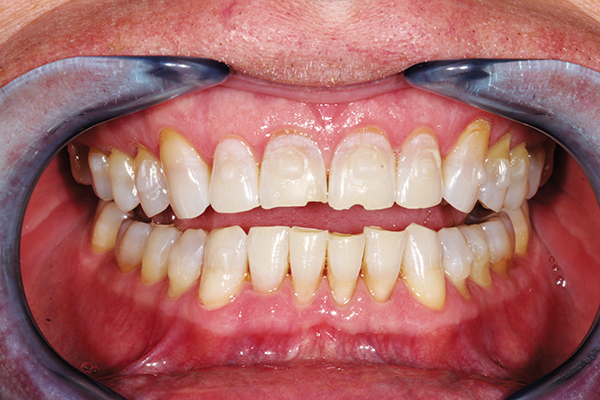

A fearful patient seeking multidisciplinary changes needed treatment of decayed bilateral lower molars. The goal was to preserve tooth structure and restore directly (Fig. 4).

Fig. 4 Fig. 5

Restoring the posterior molars was easily done with BRILLIANT EverGlow. It was easily condensed and sculpted to anatomical contours and polished to a lifelike shine (Fig. 5).